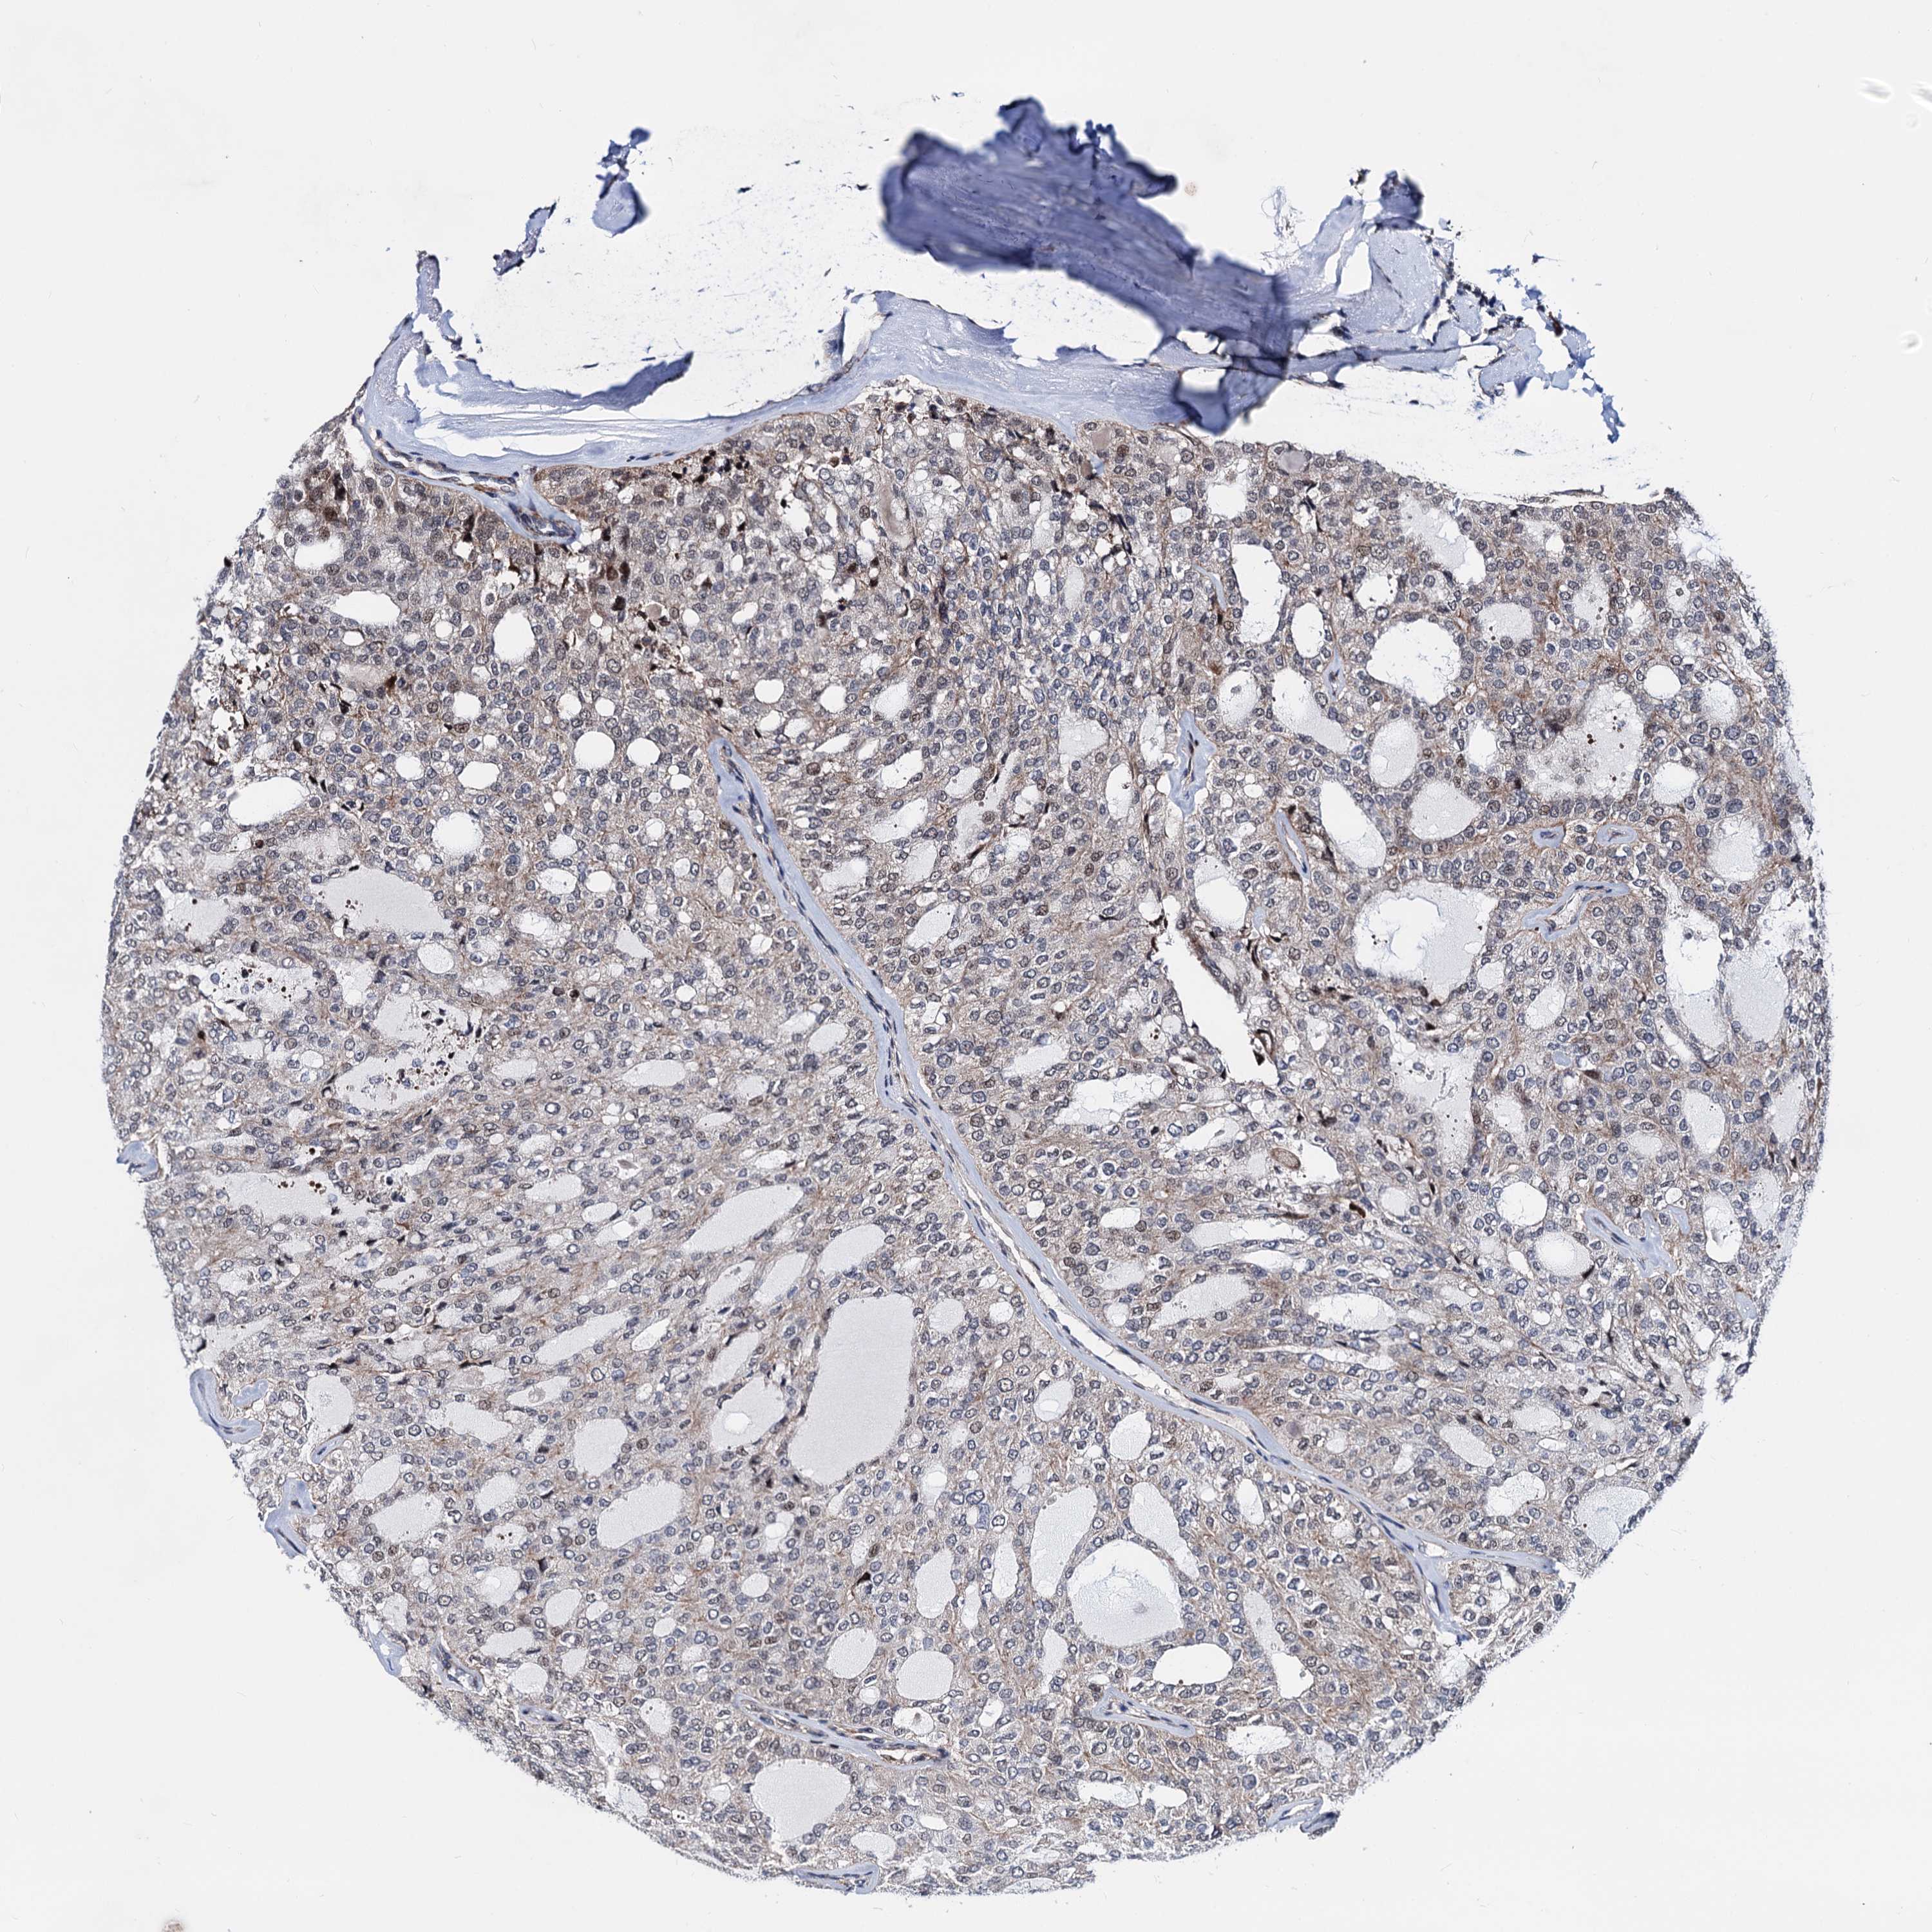

THYROID CANCER - Protein expressioni

A mouse-over function shows sample information and annotation data. Click on an image to view it in a full screen mode. Samples can be filtered based on level of antibody staining by selecting one or several of the following categories: high, medium, low and not detected. The assay and annotation is described here.

Note that samples used for immunohistochemistry by the Human Protein Atlas do not correspond to samples in the TCGA dataset.

Antibody stainingi

Antibody staining in the annotated cell types in the current human tissue is reported as not detected, low, medium, or high, based on conventional immunohistochemistry profiling in selected tissues. This score is based on the combination of the staining intensity and fraction of stained cells.

Each image is clickable and will lead to virtual microscopy that enables deeper exploration of all samples and also displays staining intensity scores, fraction scores and subcellular localization as well as patient and tissue information for each sample.

Antibody HPA040126

Staining

High

Medium

Low

Not detected

Intensity

Strong

Moderate

Weak

Negative

Quantity

>75%

75%-25%

<25%

None

Location

Nuclear

Cytoplasmic/membranous

Cytoplasmic/membranous,nuclear

Papillary adenocarcinoma, NOS

Follicular adenoma carcinoma, NOS